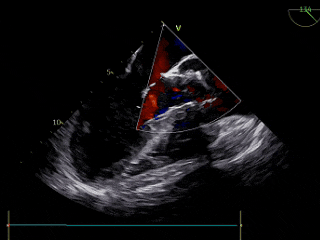

TEE

左室短轴切面见二叶瓣畸形、长轴切面见重度反流。

术后TEE评估

TEE超声评估微量瓣周漏,测压差7mmHg,反流改善明显。